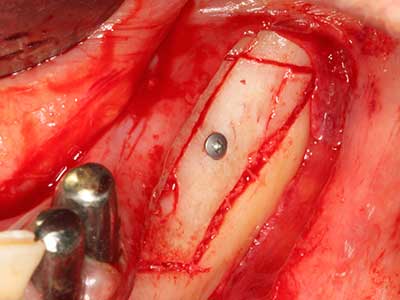

Abb. 18: Präparation eines Kortikalis-Deckels mit der Piezo-Knochensäge (Piezomed, W&H).

Sollen chirurgische Eingriffe mit unmittelbarer Knochenbeziehung an empfindlichen Strukturen wie Blutgefäßen oder Nerven erfolgen, so bergen rotierende Instrumente ein erhebliches Potential an iatrogener Schädigung. Gerade bei Nervdarstellungen nach iatrogener Schädigung, oder aber im Zuge einer Nervlateralisation für resektive und rekonstruktive Eingriffe oder Implantatinsertionen können piezoelektronische Geräte hilfreich sein Knochendeckel zu präparieren und nervnahe Hartgewebsanteile zu entfernen (Abb. 17-20). Ein leichter Kontakt des Nervstrangs zur Piezospitze bleibt dabei in der Regel folgenlos – allerdings kann eine unvorsichtige Vorgehensweise mit sägeartigen Bewegungen bzw. Ansätzen bei noch vorhandener knöcherner Unterlage durchaus temporäre oder aber auch permanente Nervschädigungen verursachen. Das Risiko einer solchen Schädigung wird jedoch als wesentliche geringer eingeschätzt als unter Anwendung von Säge- oder Fräsinstrumenten (Pereira, Gealh et al. 2014).